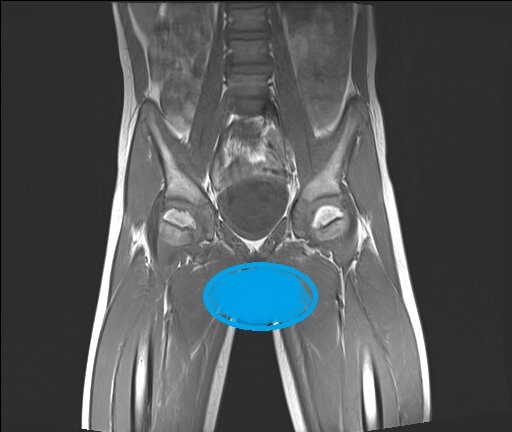

В пятницу вечером информацию на сайте по поводу Егора выложила, на следующий день с утра первым делом принялась читать ответы. Врачи видят только Пертеса или возможно Пертеса, с разной степенью уверенности. Вот куда девается верх головки правого бедра? Но зато меня успокоили насчет онкологии, что вот ее совсем никто не видит, а консультация с онкологом входит в обязательный протокол обследований при данном заболевании. Онкологии нет это хорошо, то что видят Пертеса, не очень, то что вероятно, а не точно, немного обнадеживает. Но в целом ситуация не очень. Правда расстраиваться времени не было. Супчик я с вечера сварила, а вот до второго руки не дошли. Так что закрыла ноутбук и быстренько закинула отвариваться макароны и сосиски. Потом подняла ребятишек. Лизка отправила в школу, Маргариту и Егора лечить глаза (повел дедушка). Сегодня последний день. Все отходили без пропусков 10 дней. А мы с Полей пошли на МСЭ. Все прошло очень доброжелательно, но на удивление долго. Я так долго то

В пятницу вечером информацию на сайте по поводу Егора выложила, на следующий день с утра первым делом принялась читать ответы. Врачи видят только Пертеса или возможно Пертеса, с разной степенью уверенности.

Вот куда девается верх головки правого бедра?

Но зато меня успокоили насчет онкологии, что вот ее совсем никто не видит, а консультация с онкологом входит в обязательный протокол обследований при данном заболевании.

Онкологии нет это хорошо, то что видят Пертеса, не очень, то что вероятно, а не точно, немного обнадеживает. Но в целом ситуация не очень.